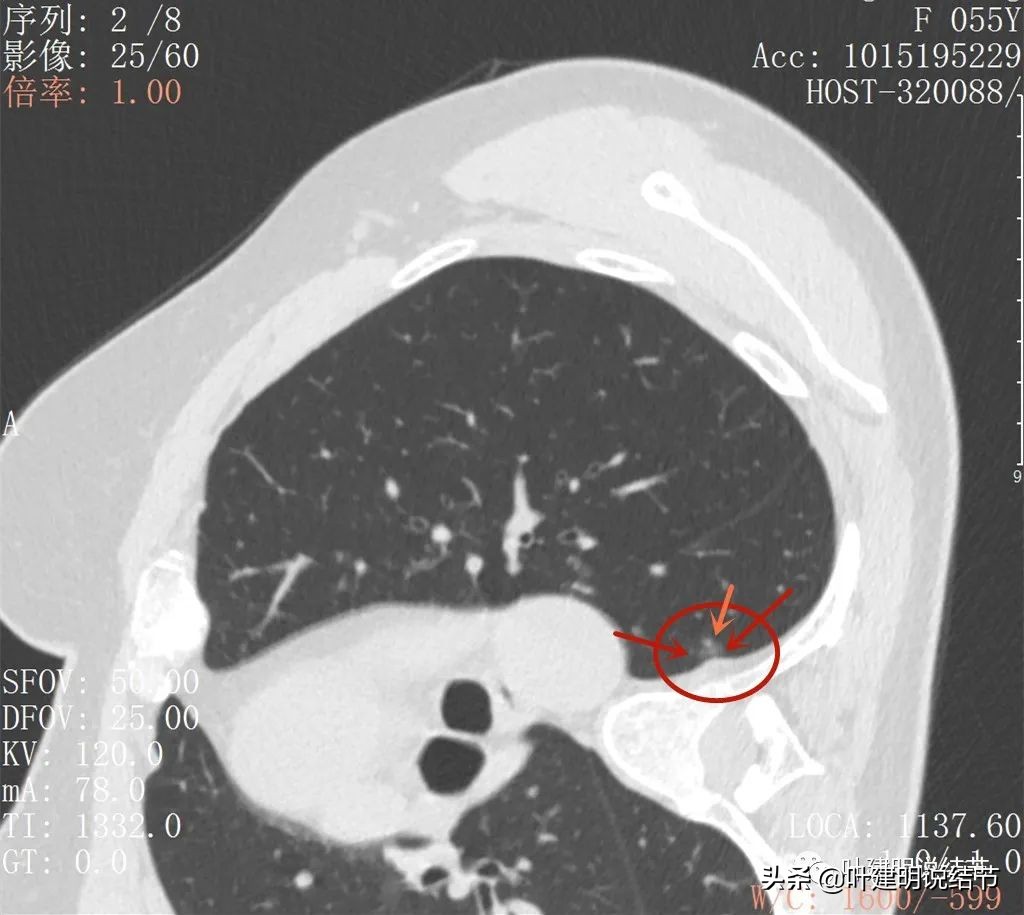

再来看2022年6月的CT图像:

小病灶轮廓清,是磨玻璃结节(红色箭头),有血管贴边或穿行(桔色箭头)

密度是磨玻璃,稍不均质,似乎略见胸膜牵拉(蓝色箭头)

整体轮廓清